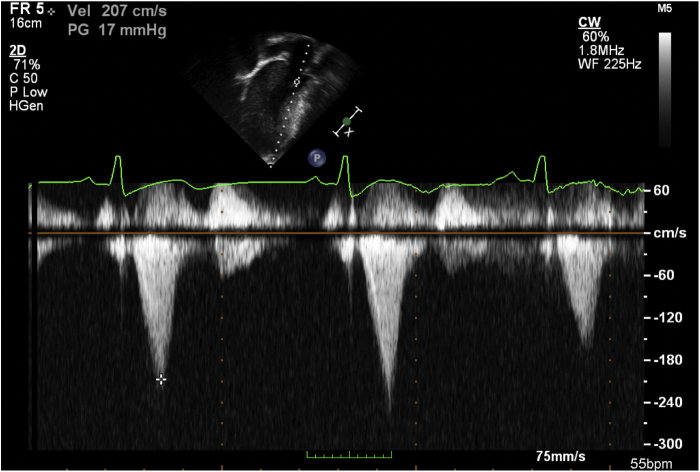

Figure 3.

Two-dimensional TTE apical 4-chamber view with continuous-wave Doppler across the left ventricular outflow tract showing a 17 mm Hg gradient.